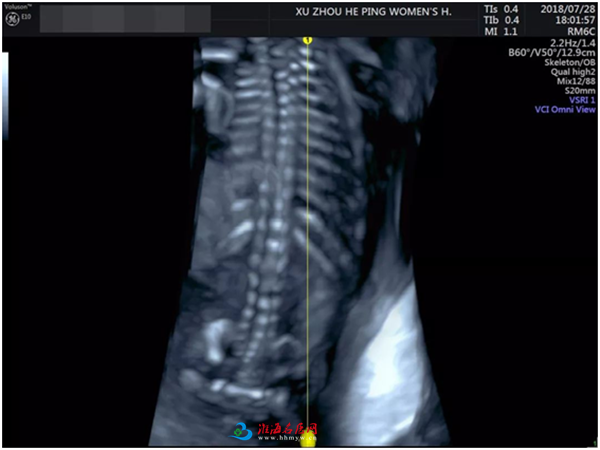

▼胎儿脊椎骨骼的情况也筛查得非常仔细,脊椎也很健康哦